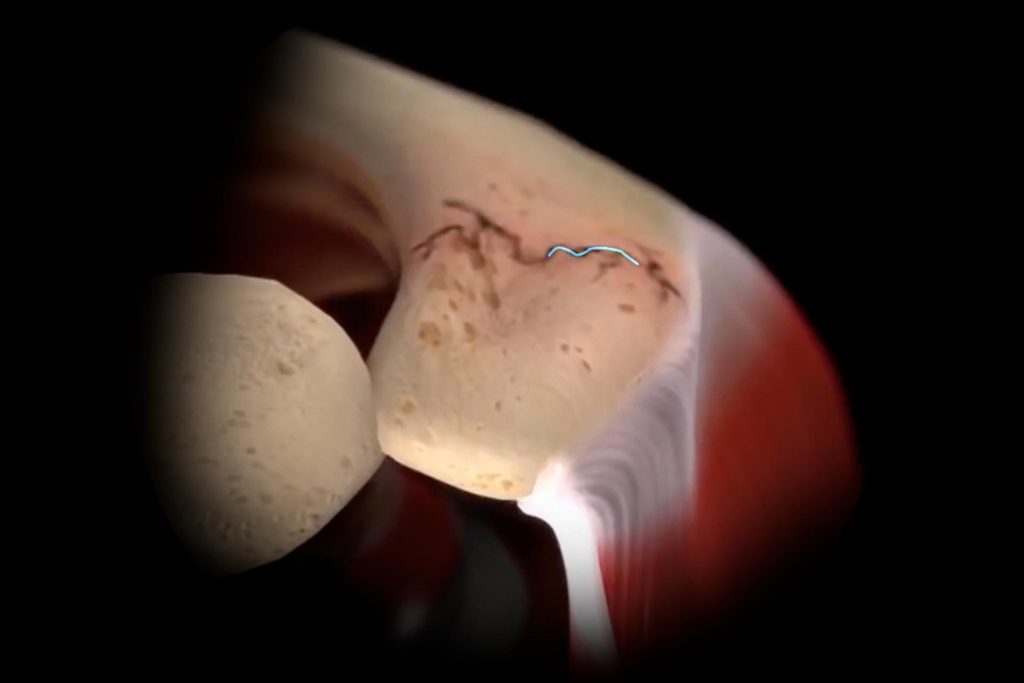

GPS Shoulder

Preoperative planning with real-time intraoperative instrument guidance and verified implant placement for TSA.